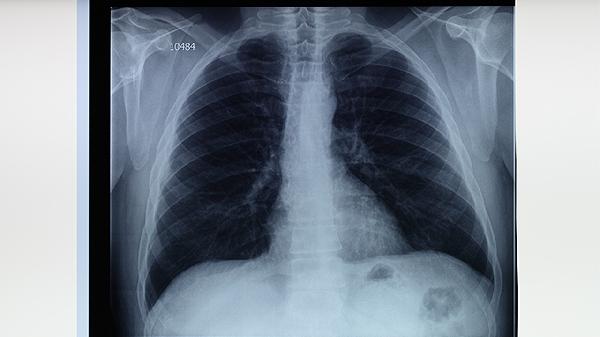

肺结核患者出现舌苔厚白时,建议每日用软毛牙刷轻刷舌面,避免进食辛辣刺激性食物。保持充足睡眠有助于增强免疫力,可练习八段锦等温和运动促进气血运行。注意监测体温变化,若舌苔持续增厚伴发黑或裂纹,需及时复查胸部CT排除病情进展。治疗期间应定期进行痰涂片检查,观察结核杆菌转阴情况。